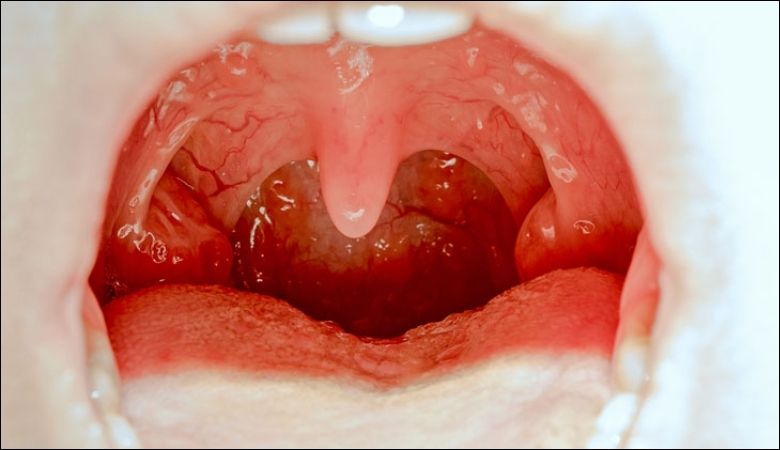

Hình ảnh nổi hạt ở cuống lưỡi

Lưỡi nổi hạt đỏ là tình trạng trên bề mặt hoặc vùng cuống lưỡi xuất hiện các đốm hoặc mụn nhỏ có màu đỏ, đôi khi sưng tấy, rát hoặc đau nhức. Theo Hiệp hội Nha khoa Hoa Kỳ (ADA), tình trạng thay đổi màu sắc, hình dạng hoặc cấu trúc lưỡi có thể là dấu hiệu cảnh báo của các bệnh lý răng miệng như viêm, nhiễm trùng hoặc thậm chí là ung thư miệng nếu kéo dài mà không điều trị.

- U Nhú Tiền Đình Papillomatosis

Là tình trạng tế bào gai ở lớp biểu mô miệng phát triển quá mức, hình thành các nốt thịt nhỏ màu đỏ hồng có cuống riêng biệt. Thường không đau nhưng có thể gây cộm vướng.